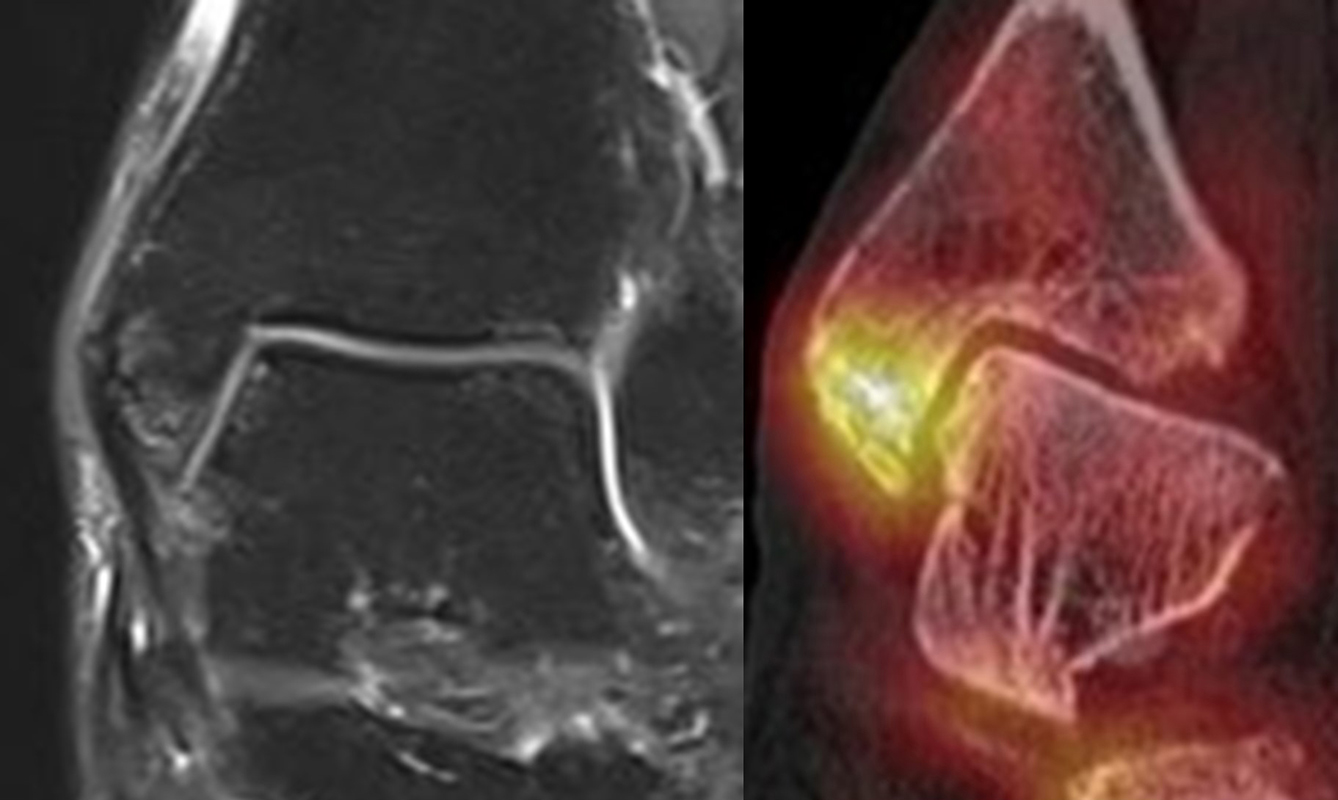

Abbildung 2.2.

Bilder eines Patienten mit Z. n. mehrfachen Sprunggelenksdistorsionen in der Vergangenheit, besonders heftige Distorsion des linken Sprunggelenkes 5 Wochen vor der Untersuchung. Die SPECT/CT zeigt eine instabile osteochondrale Läsion mit deutlicher Aktivierung.

Zum Lesen der Bildbeschreibung und zur Vollansicht bitte das Bild anklicken. Bild: H. C. Rischke